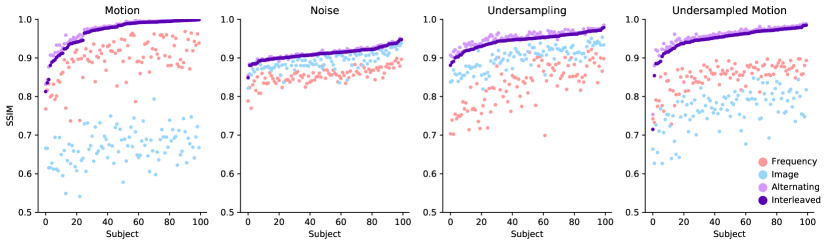

4.1.2 Results

Fig. 4 reports reconstruction quality statistics for all four types of simulations described in Section 4.1.1: motion, noise, undersampling, and motion combined with undersampling. The Interleaved and Alternating architectures outperform the baseline architectures for nearly every task and subject. Across all tasks and nearly all subjects, the Interleaved and Alternating architectures are quite similar in numerical performance. Sample image reconstructions for the motion, motion with undersampling and denoising tasks are shown in Figs. 5-7. Qualitatively, for each task, the Frequency network provides a blurry version of the ground truth image. The Image network provides a reconstruction which effectively removes ‘background’ effects but has limited success in correcting these artifacts within the image. In contrast, the Interleaved and Alternating networks provide sharper, high-quality reconstructions across all tasks. Further, the frequency space reconstructions provided by those networks appear the most faithful to the ground truth frequency data.